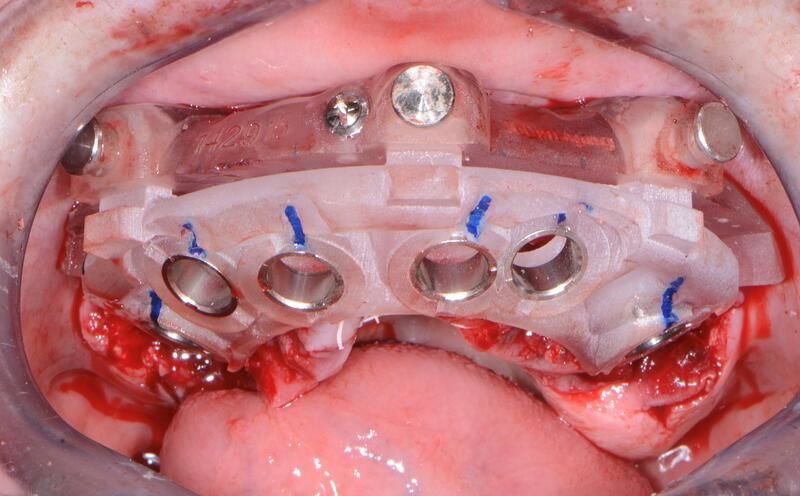

全口組合式導(dǎo)板病例

術(shù)中過(guò)程

完成植入后全景照片